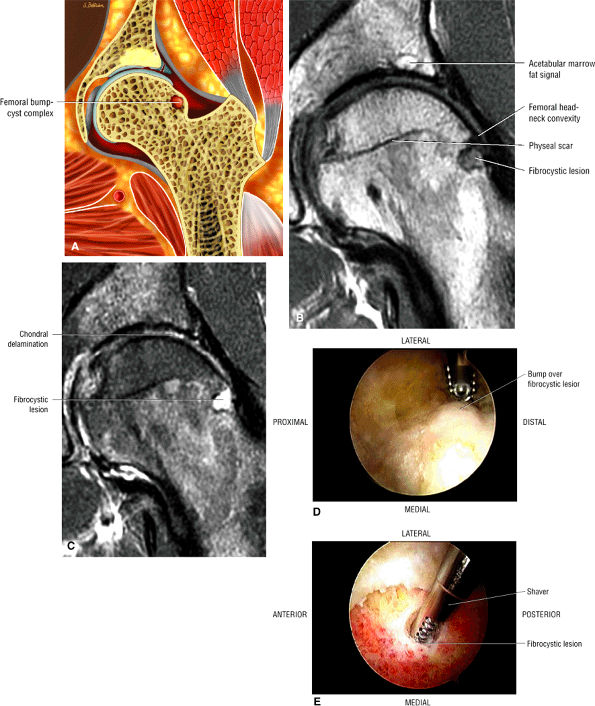

Dysplastic bump in the anterolateral femoral head-neck junction associated with cam-type femoroacetabular impingement

An enlarged or hypertrophied labrum may occur in patients with mild DDH.17 We have observed a femoral head chondral crease (Fig. 3.66) in these patients, creating a demarcation trough medial to a femoral head bump immediately proximal to the physeal scar. Patients who demonstrate femoroacetabular impingement (or lateral acetabular rim syndrome in DDH) also have direct impingement between the lateral acetabular labrum and the femoral head.